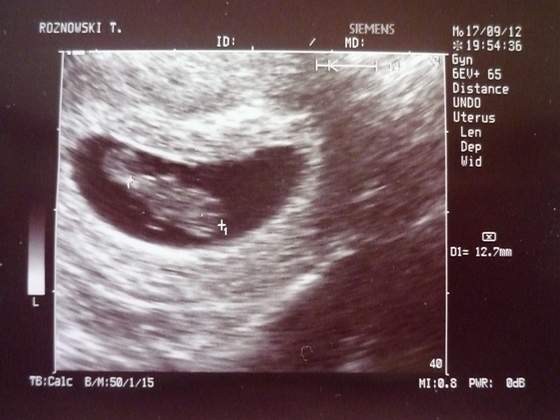

dwa kawałki nieba mam